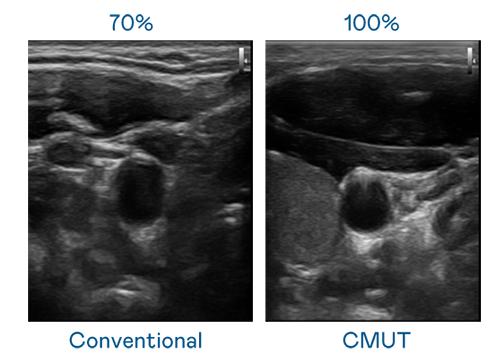

CMUT 技术是一种用电容式微机电元件来产生超音波讯号的技术。与传统 PZT 压电式技术相比,CMUT 频宽增加 30%,更宽频的超音波讯号让影像解析度大幅提升,是实现高影像品质医疗超音波扫描、促进精准医疗发展的关键技术。

超音波影像的解析度高低,首先取决于探头能发出的讯号频宽。大庄家 CMUT 可提供高清晰的超音波讯号,提供高频宽、高灵敏度、影像纹理细节更高的超音波影像,协助医护人员缩短影像判读时间及利用精准的医疗影像进行诊断。